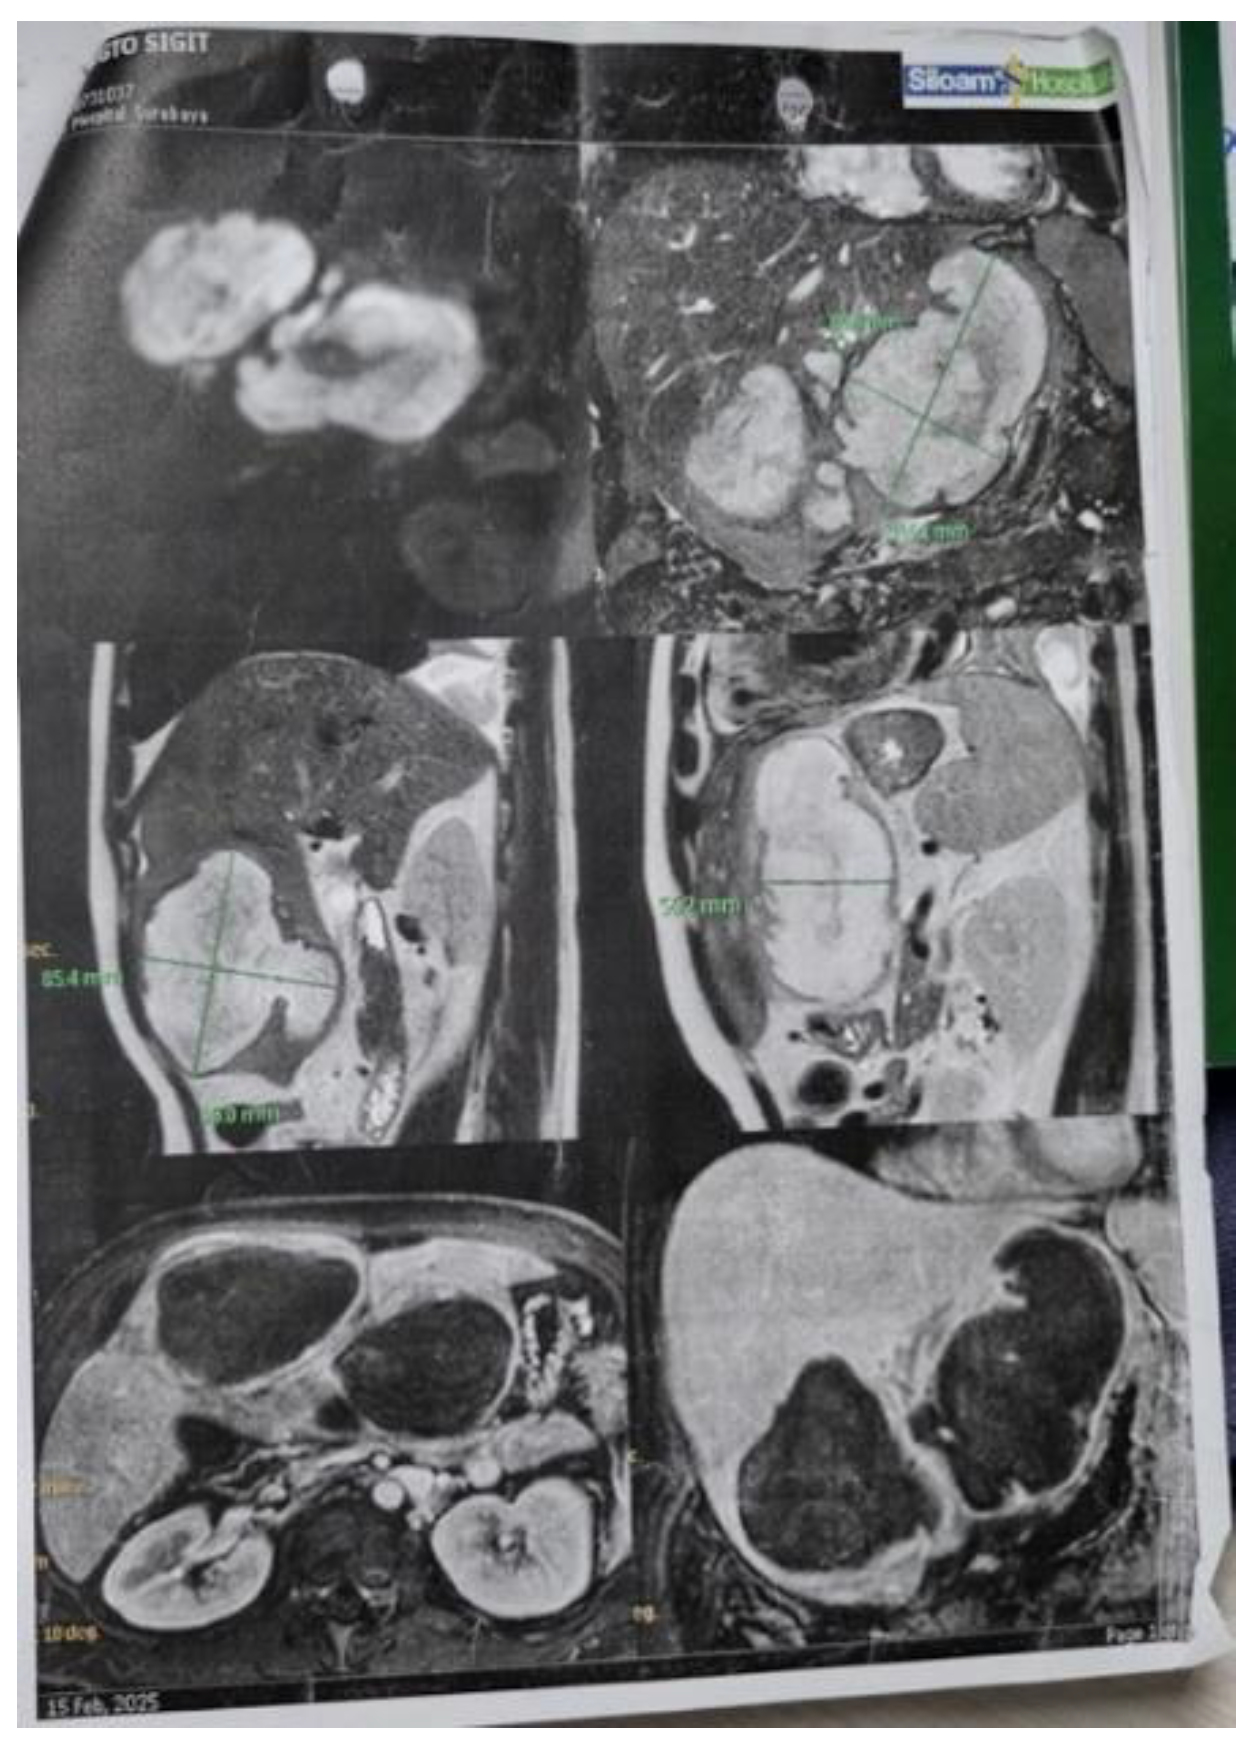

Background: Liver abscesses represent an atypical yet potentially life-threatening complication of bacterial, fungal, protozoal, and helminthic infections. Frequently, the clinical findings associated with liver abscesses are nonspecific, necessitating a reliance on imaging for diagnosis. It is uncommon for a liver abscess to radiographically resemble a malignant liver tumor such as hepatocellular carcinoma (HCC). Here, we present the case of a 45-year-old male who was initially diagnosed with HCC (BCLC C) but was subse-quently found to have a liver abscess following biopsy. Case Presentation: A male patient, 45, presented with stiffness and pain in the right upper abdomen. He complained of nausea and vomiting since 10 days before admission as well. All supportive imaging suggested a diagnosis of HCC. A liver abscess was detected during a biopsy. A liver ultrasound-guided FNAB showcased chronic, suppurative in-flammation with negative acid-fast bacilli on Ziehl-Neelsen staining. The patient sub-sequently developed a complication of middle hepatic artery bleeding and underwent immediate embolization. Discussion: In fact, a liver abscess can be the initial manifestation of HCC. Patients tend to have a poorer prognosis because the diagnosis of a liver abscess often delays the discovery of the underlying HCC. Radiographically, liver abscesses range from well-circumscribed cystic lesions with an enhancing rim to heterogeneously enhancing mass-like lesions, which are sometimes indistinguishable from liver neoplasms. However, it is so scarce that a liver abscess may radiographically mimic HCC. Conclusion: Assessing liver abscess is somewhat complicated since the symptoms vary a lot. Therefore, a correct and exact diagnosis entail a combination of more comprehensive clinical and supporting examinations.